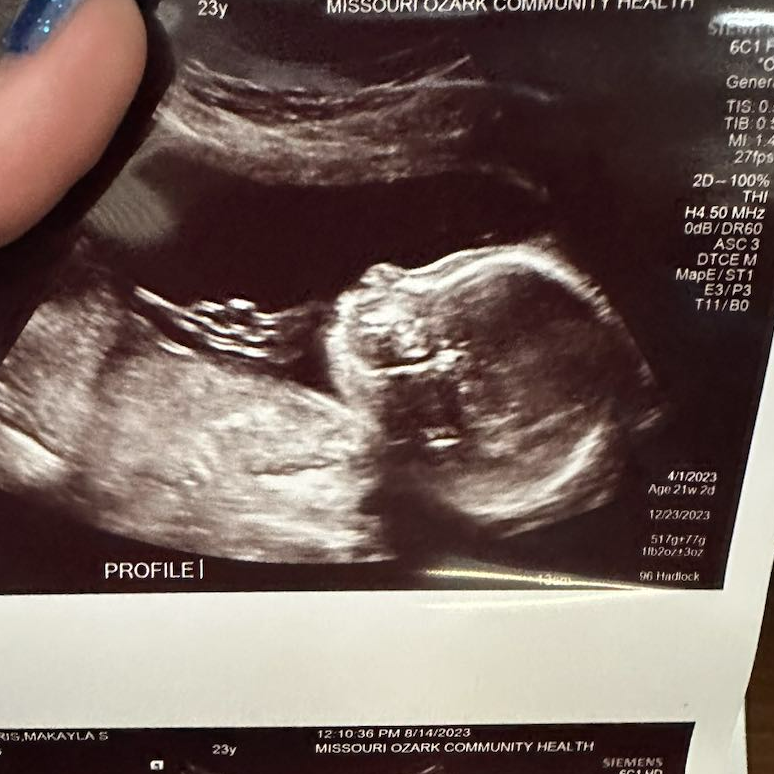

来自密苏里州的爱妈M今天如期前往妇产科进行了检查,宝宝已经21周大了。在检查中,可以清晰地看到了一个可爱的小男孩!在美国PGS技术不仅可以检测胚胎的染色体异常,还可以实现性别的选择。

这项技术可以帮助准父母能够更好地规划自己的家庭。和爱妈M匹配的准妈妈非常的高兴,她目标是能够迎来属于自己的两个宝宝,期待着她未来家庭的美好发展!

宝宝的脸